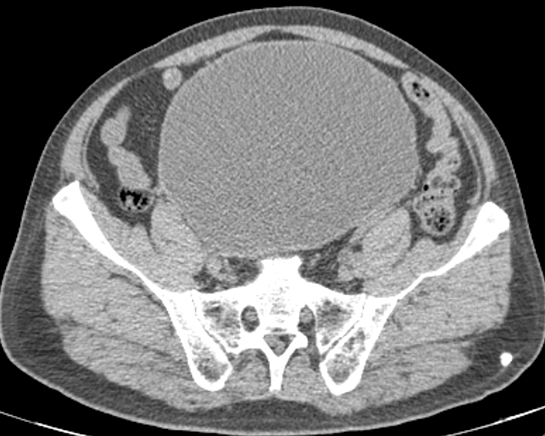

病例二

患者,男,49 岁,因尿频尿急 1 年,体检发现膀胱占位 5 天入院。

膀胱充盈尚可,后壁略增厚、毛糙,腔内未见明确异常密度影。前列腺体积不大,见结节状钙化影,双侧精囊腺略饱满,周围脂肪间隙浑浊。

好发部位位于膀胱三角区及膀胱颈部,CT 表现为膀胱壁增厚、隆起性病变,多>5 mm,宽基底,病灶边缘光滑,隆起内可见囊变或钙化。增强后轻度强化,较邻近正常膀胱壁密度相似,膀胱外壁光整,局部输尿管壁可受累,一般无盆腔淋巴结肿大。影像学分型:草坪型-膀胱壁内节段性增厚;弥漫型-膀胱壁弥漫性增厚;结节型-膀胱内壁结节样隆起,表面光整、宽基底(钝角)。本病例 1 属于弥漫型,病例 2 属于草坪型。